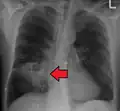

Pulmonary abscess on CXR -

Lung abscesses are often on one side and single involving posterior segments of the upper lobes and the apical segments of the lower lobes as these areas are gravity dependent when lying down. Presence of air-fluid levels implies rupture into the bronchial tree or rarely growth of gas forming organism.